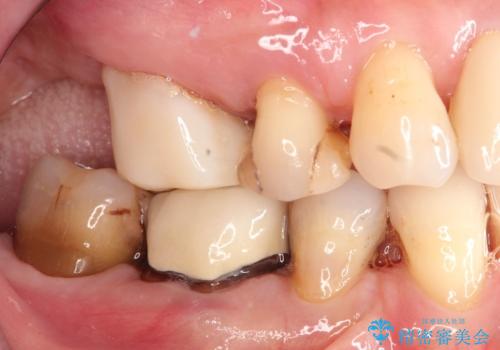

歯周病の進行した歯の抜歯。オールセラミッククラウン

- 以前に他院にて治療した歯が痛いことを主訴に来院されました。

最後方臼歯は根尖部まで歯周病が進行しており、抜歯を行なったのち、残存歯は歯周外科を行なったのちオールセラミッククラウンにて修復治療を行なっています。

歯周外科を行う事により歯周ポケットを除去し予知性の高い治療を行うことができますが治療期間がかかります。